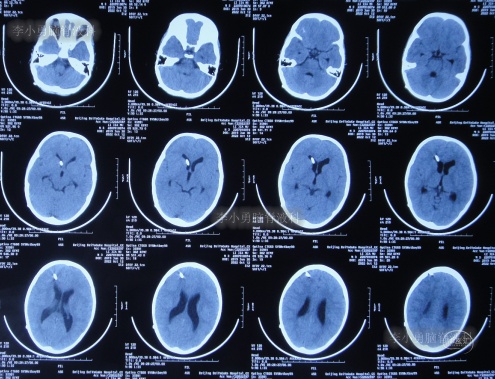

第3家医院治疗16天即2022年6月9日,不但依然发热,而且查头颅CT示脑室稍扩张(图-3)。

图-3:2022年6月9日头颅核磁